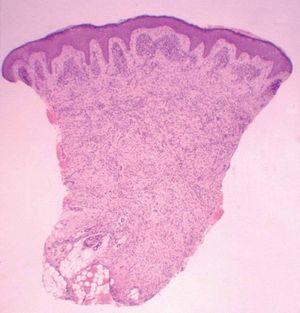

Se realizó una biopsia de la lesión del labio mayor. En el estudio histológico llamaba la atención la presencia de una condensación celular en banda subepidérmica (capa de cámbium) (fig. 2). Se apreció una infiltración cutánea por una neoplasia mesenquimatosa constituida por elementos rabdomioblásticos atípicos redondeados o fusiformes (fig. 3). Las células se disponían de forma vagamente estoriforme sobre una matriz mixoide. Con técnicas de inmunohistoquímica se evidenció positividad para vimentina, MyoD1 y marcadores de diferenciación muscular (actina HHF35, desmina y mioglobina). Las células neoplásicas eran negativas para queratina AE1/AE3, EMA, HMB45, S100, enolasa neuronal específica, CD99, CD34 y CD45.

El rabdomiosarcoma botrioides es un subtipo del tipo embrionario que representa aproximadamente el 6 % del total de los rabdomiosarcomas 8 . La palabra botrioides deriva del griego botrys (racimo) y eidos (aspecto), ya que se trata de una masa constituida por formaciones polipoides edematosas agrupadas, con una característica apariencia de racimo de uvas. La mayoría de los rabdomiosarcomas botrioides aparecen en órganos huecos con revestimiento mucoso, desde donde pueden extenderse hacia la superficie corporal. El libre crecimiento en cavidades corporales o hacia la superficie explica su apariencia característica. Aunque existen algunos casos descritos, la aparición cutánea primaria es muy rara 4,9-12 . Microscópicamente, el rabdomiosarcoma botrioides muestra una relativa hipocelularidad y una abundancia de estroma mixoide, lo que puede hacernos obviar la naturaleza maligna de la lesión. El rasgo más importante para el diagnóstico es la presencia de la capa de cámbium 1 , denominada así por asemejarse a la capa de células entre la corteza de un tronco y la madera, y que se caracteriza por una condensación subepitelial de células tumorales separadas de un epitelio intacto por una banda de estroma laxo. Las células tumorales varían en apariencia desde células pequeñas primitivas, hasta células con evidente diferenciación rabdomioblástica 1

Fig. 2.—La capa de cámbium aparece interrumpida por la presencia de anejos cutáneos. (Hematoxilinaeosina, ×40.)